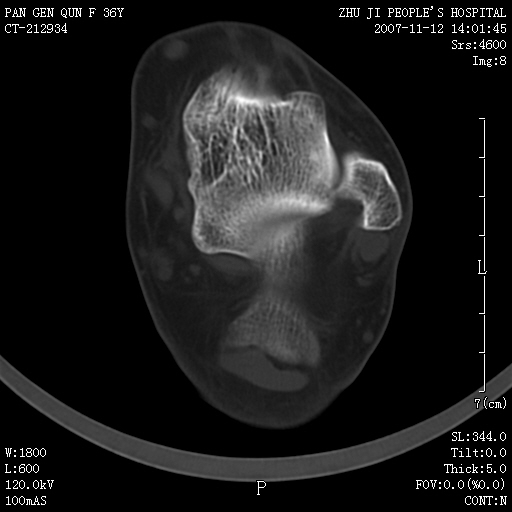

标题: CT10417:F36Y,跟骨跟腱附着处下方骨质密度影,请会诊. [打印本页]

标题: CT10417:F36Y,跟骨跟腱附着处下方骨质密度影,请会诊.

跟骨结节后部肿块半年,无明确外伤史,及红肿热痛.

跟腱附着处骨化致骨化性肌炎。

跟腱附着处骨化致骨化性肌炎